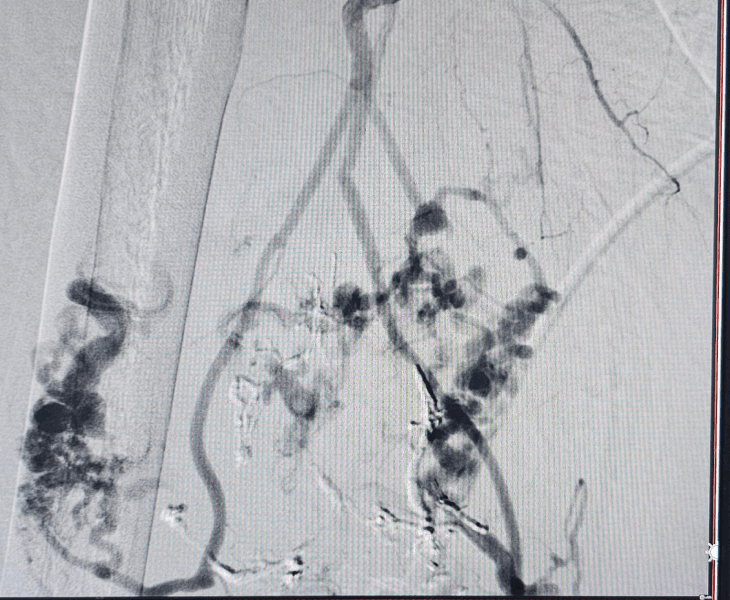

Large vascular malformation in leg

We identify the feeding vessels and the malformation “nidus” using Doppler, MRI and angiography to plan a safe, targeted approach.

2. Image‑Guided Treatment

Depending on the lesion, we perform embolization and/or sclerotherapy to reduce abnormal flow and shrink the malformation in a controlled manner.